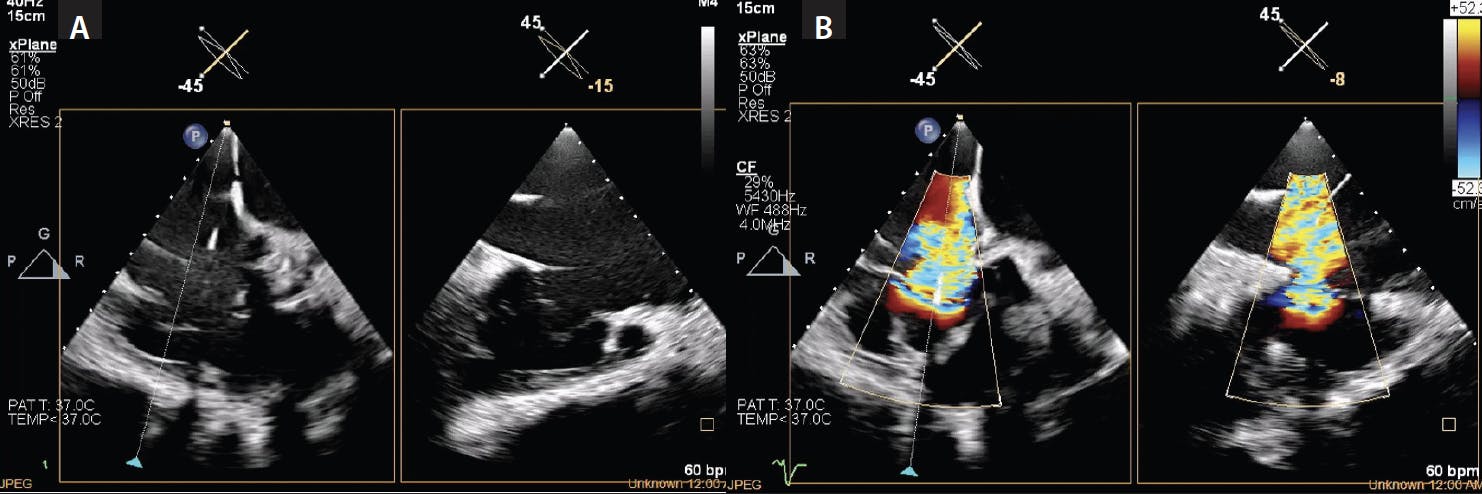

Figure 5. Biplane view showing the TV anatomy (A). Biplane images are obtained to determine the area of maximum regurgitation (B) and full anatomic assessment with an RV inflow/outflow view.

The initial 3D ICE imaging for the TV is the home view position in the right atrium (RA) with and without color to identify all three TV leaflets and origination of the TR jet (Figure 4). Biplane images are obtained to determine the area of maximum regurgitation and full anatomic assessment, including an RV inflow/outflow view (Figure 5). A multiplane reconstruction (MPR) view is obtained by placing the crosshair markers across the TV, creating a 3D en-face view of the TV in real time. Ideally, the aortic valve is placed at the nine o’clock position to help identify all leaflets in a consistent manner, according to this anterior landmark. From this view, anterior, posterior, and septal leaflets are identified (Figure 6). The TV often has more than three leaflets. The steerable guide catheter (SGC) is identified in the RA, and the clip delivery system (CDS; Abbott) is viewed while exiting the SGC. The CDS is steered from the septal side of the RA toward the TV, and the clip is positioned above of the TV regurgitant jet.